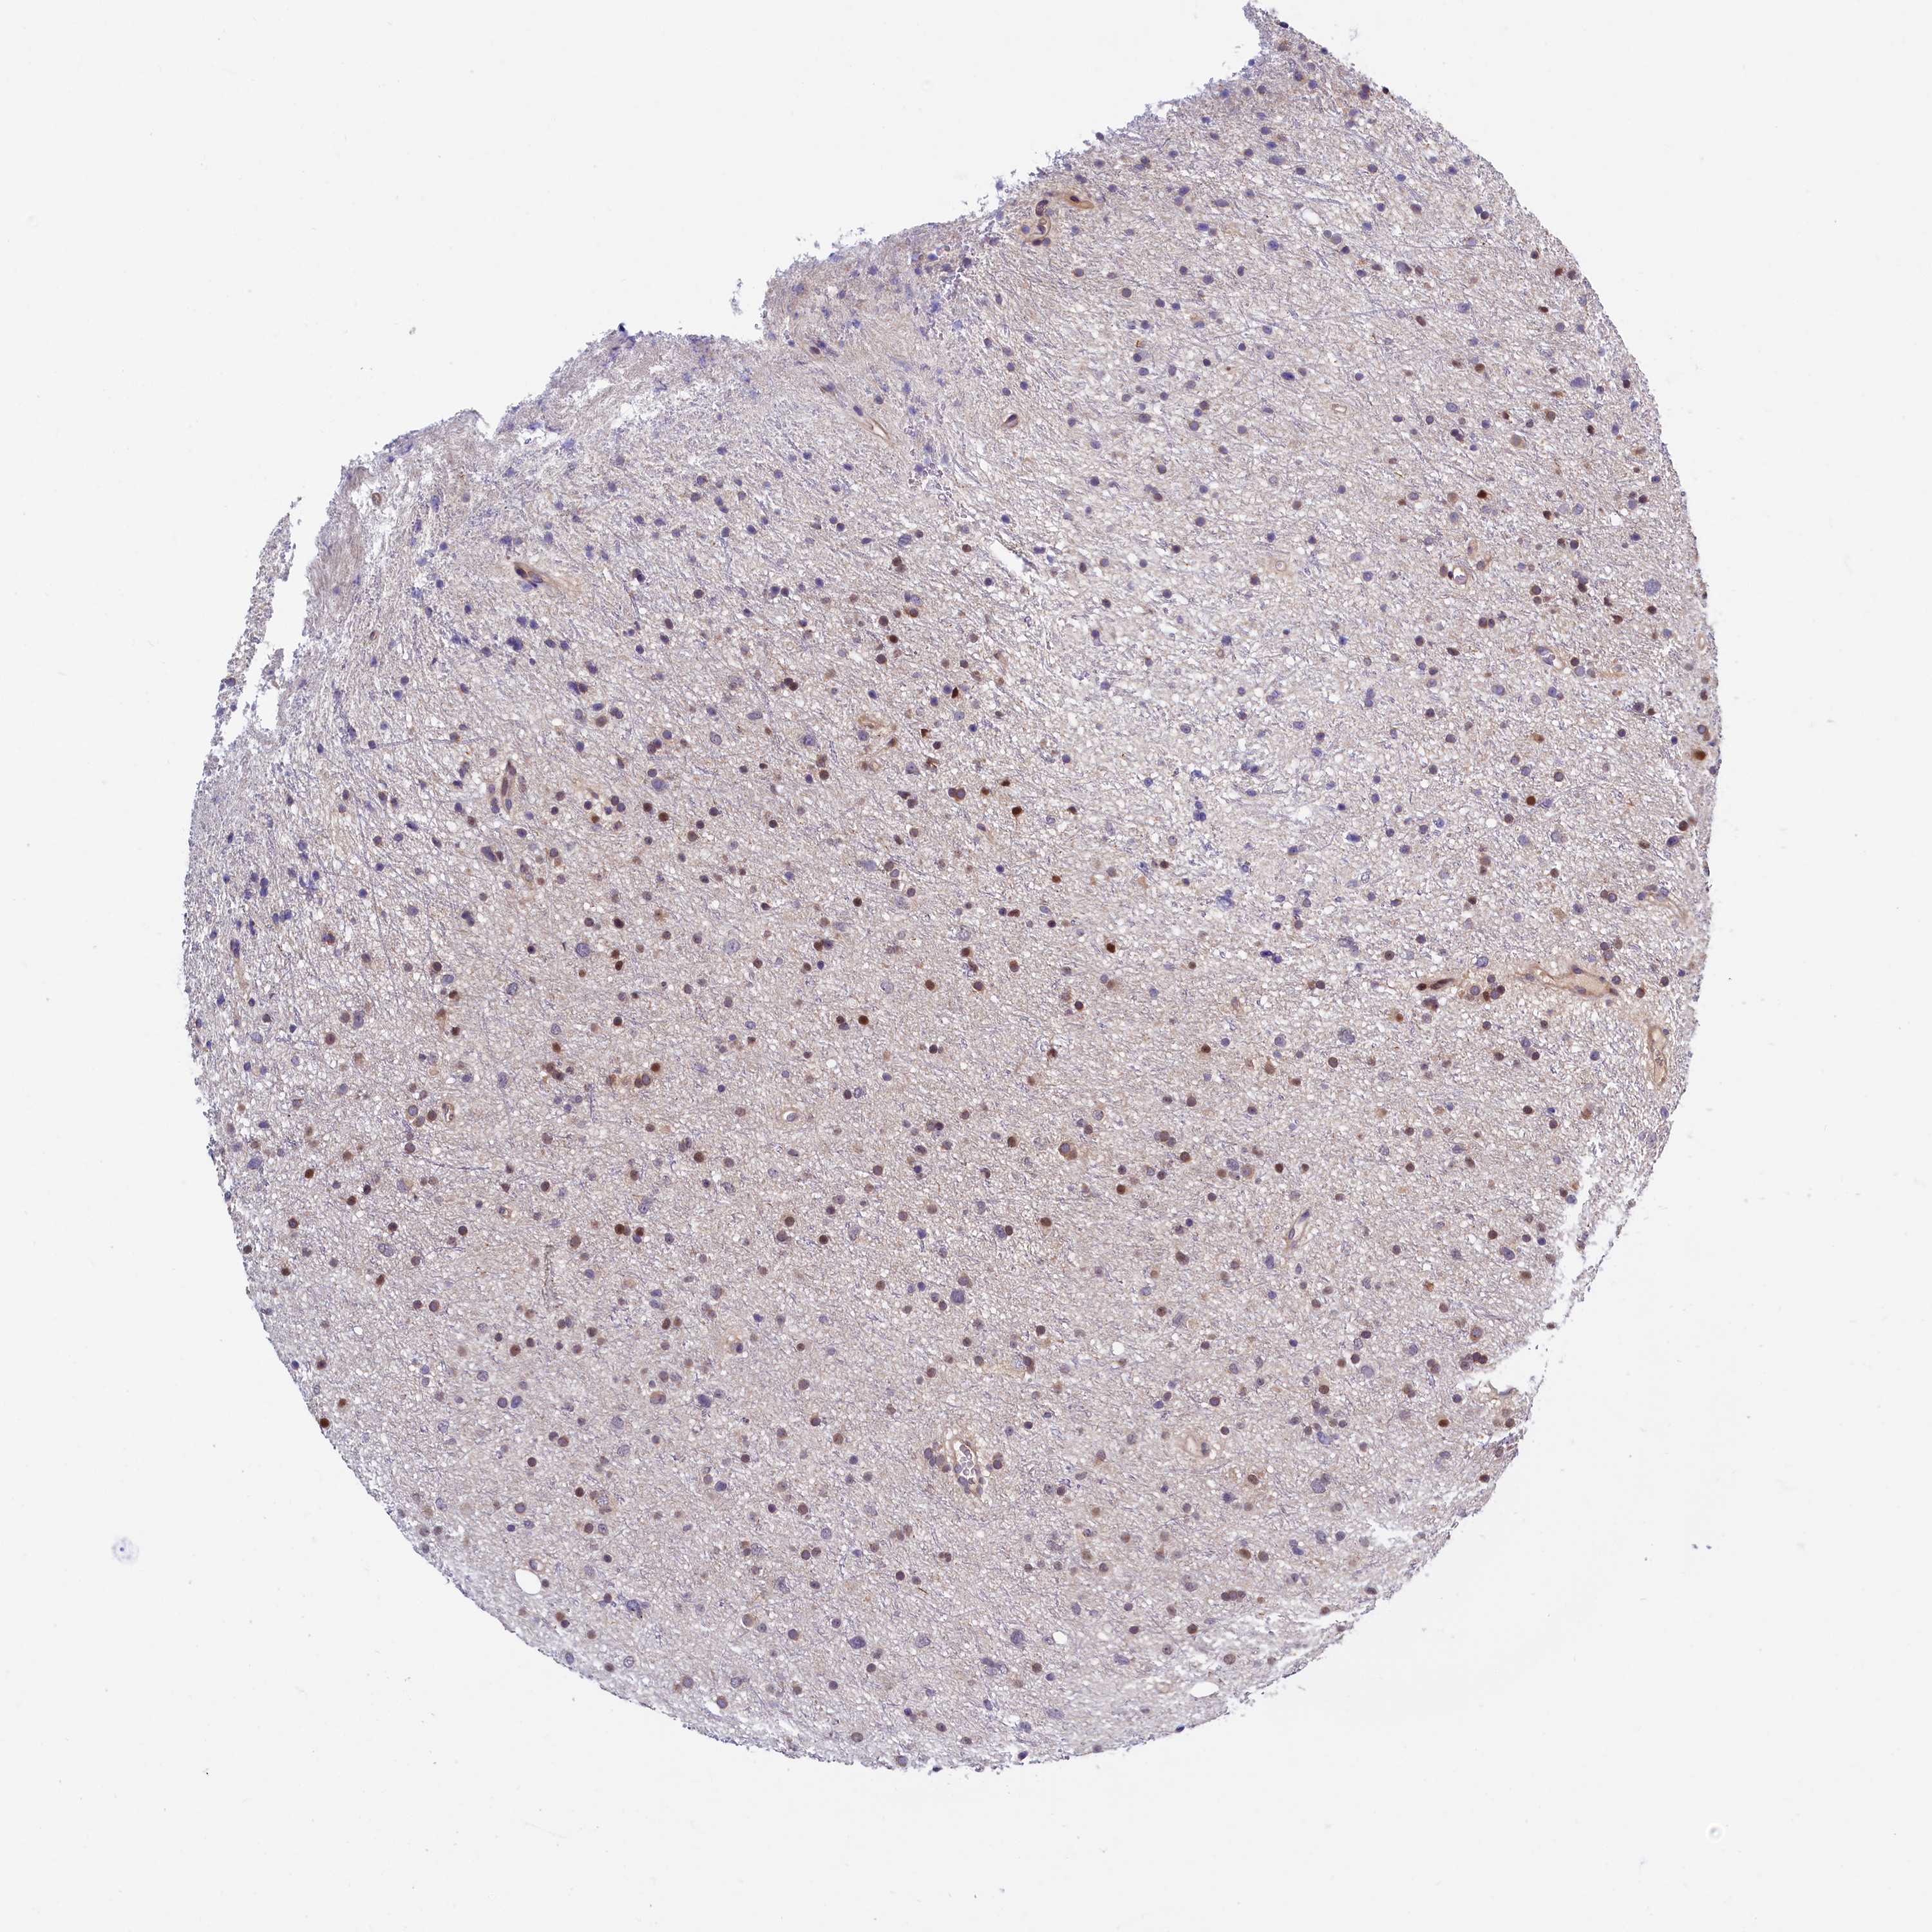

GLIOMA - Protein expressioni

A mouse-over function shows sample information and annotation data. Click on an image to view it in a full screen mode. Samples can be filtered based on level of antibody staining by selecting one or several of the following categories: high, medium, low and not detected. The assay and annotation is described here.

Note that samples used for immunohistochemistry by the Human Protein Atlas do not correspond to samples in the TCGA dataset.

Antibody stainingi

Antibody staining in the annotated cell types in the current human tissue is reported as not detected, low, medium, or high, based on conventional immunohistochemistry profiling in selected tissues. This score is based on the combination of the staining intensity and fraction of stained cells.

Each image is clickable and will lead to virtual microscopy that enables deeper exploration of all samples and also displays staining intensity scores, fraction scores and subcellular localization as well as patient and tissue information for each sample.

Antibody HPA040518

Staining

High

Medium

Low

Not detected

Intensity

Strong

Moderate

Weak

Negative

Quantity

>75%

75%-25%

<25%

None

Location

Nuclear

Cytoplasmic/membranous

Cytoplasmic/membranous,nuclear

Glioma, malignant, High grade

Glioma, malignant, Low grade